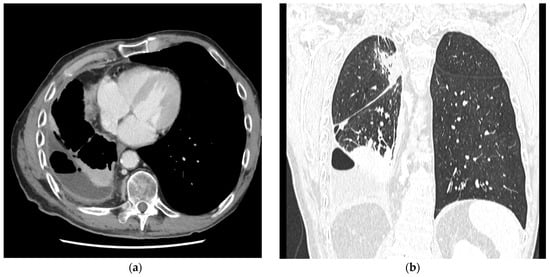

| Key radiologic findings |

|

| Aims |